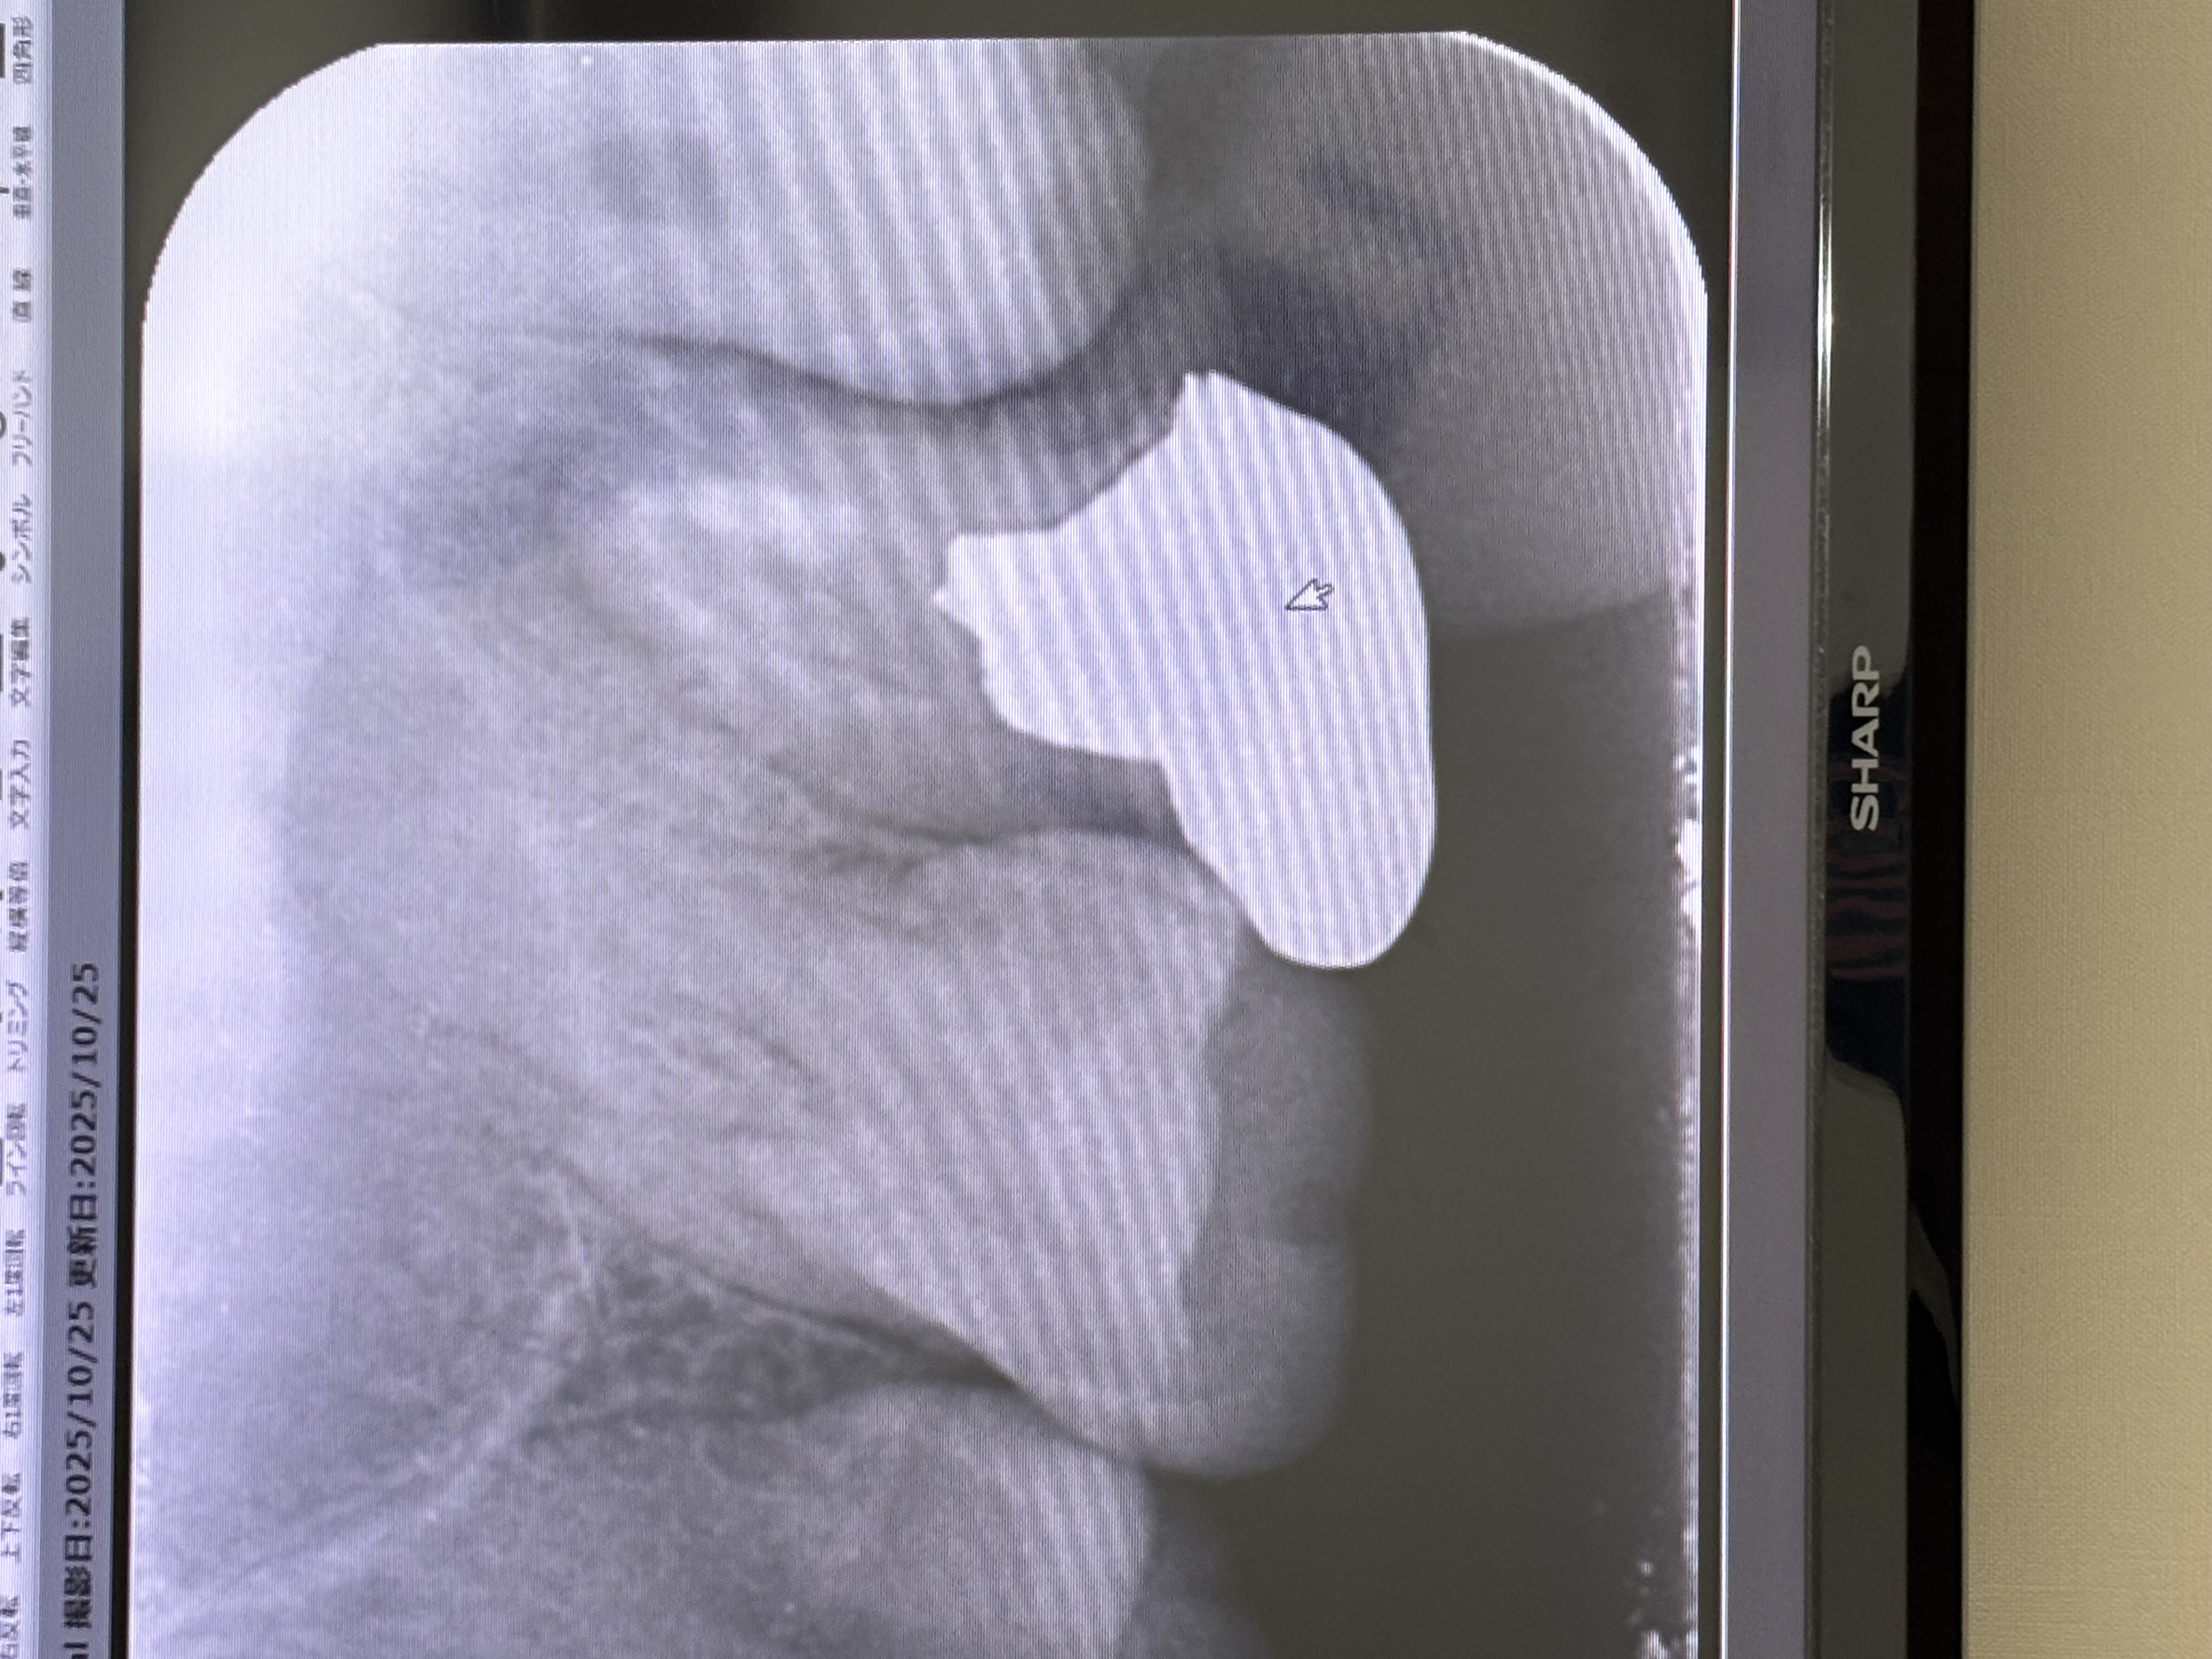

銀歯の根に膿があり痛みが続いています。回答数:2